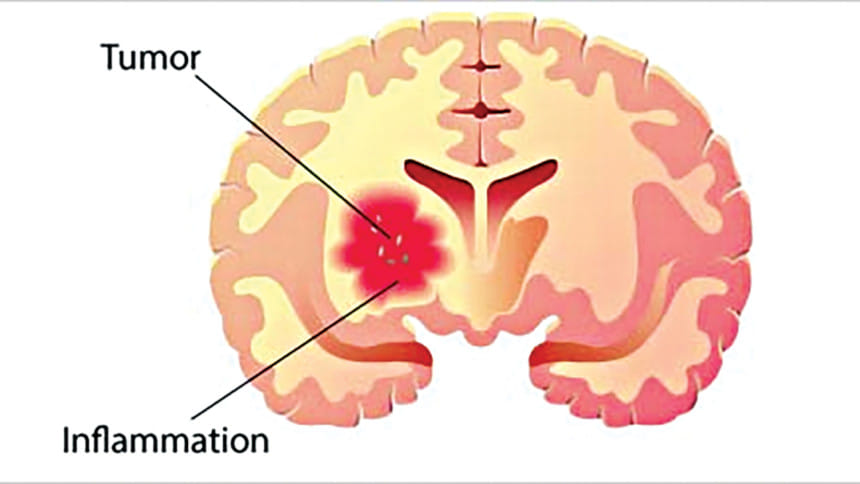

A mass of abnormal tissue growing in any part of the brain is called a brain tumour. For some unknown reason, some brain cells multiply in an uncontrolled manner. These tumours can arise from any part of the brain, the spinal cord or the nerves.

Malignant tumours or cancers are aggressive tumours that grow fast and infiltrate the surrounding brain. Sometimes they spread to other parts of the brain or spine. With aggressive and timely treatment, some of these can be cured.

Brain tumours cause headaches with or without nausea and vomiting due to the tumour growth within the tight space inside the skull. It causes swelling in the surrounding brain and can cause block the free flow of cerebrospinal fluid. Thus it results in the dilatation of the ventricles - a condition called Hydrocephalous.